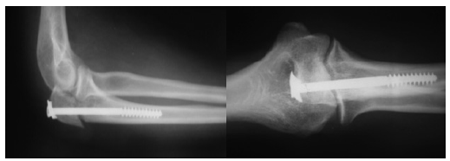

Результаты. При применении остеосинтеза длинным губчатым компрессирующим винтом у 20 из 22 больных при лечении в первые 2-3 недели наблюдалось полное восстановление функции локтевого сустава (90,9% хороших и отличных результатов в группе). В одном случае имело место перезатягивание винта, из-за чего конгруэнтность суставной поверхности локтевого отростка была нарушена (рис.4а), однако в передне-задней проекции ось кости восстановлена.

В послеоперационном периоде через небольшой разрез произведено расслабление винта на один виток, а в ходе реабилитации конгруэнтность суставной поверхности и движение в суставе полностью восстановились (рис. 5) - отросток “сел” на место.